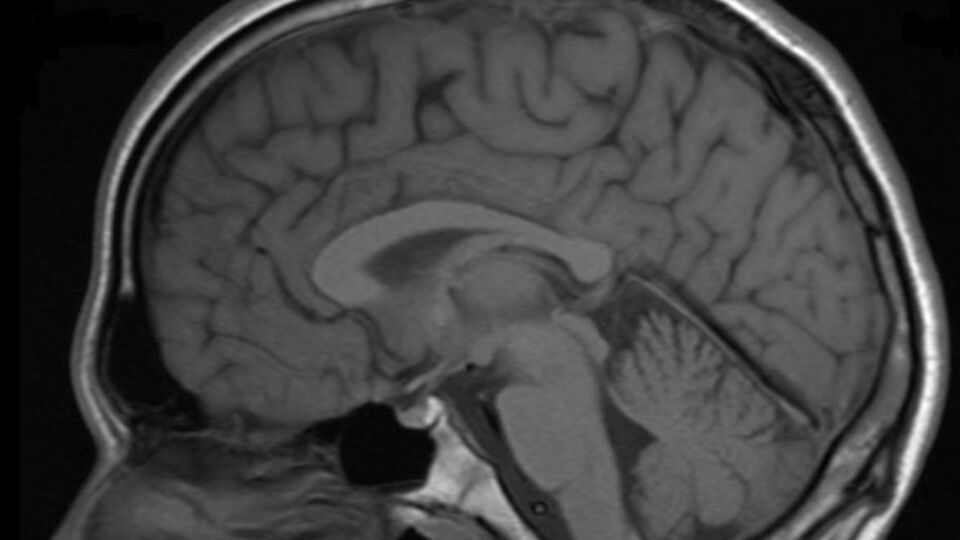

Расширенный субарахноидального конвекситального пространстваМрт головного мозга расширение субарахноидального пространства. расширение субарахноидальное конвекситальное пространство. расширение субарахноидального пространства у детей на мрт. субарахноидальное конвекситальное пространство расширено на кт.Расширение субарахноидальное конвекситальное пространство. мрт головного мозга расширение субарахноидального пространства. расширение наружных ликворных пространств головного мозга на мрт. расширение ликворных пространств головного мозга мрт.Расширенный субарахноидального конвекситального пространстваРасширенный субарахноидального конвекситального пространстваПодпаутинное субарахноидальное пространство. расширение субарахноидального пространства мозжечка. переднее субарахноидальное пространство спинного мозга. синдром арнольда-киари 1 типа.Расширенный субарахноидального конвекситального пространстваЦистерны подпаутинного пространства головного мозга. циркуляция ликвора анатомия схема. твердая мозговая оболочка головного мозга схема. субарахноидальное пространство топография.Расширенный субарахноидального конвекситального пространстваСубарахноидальное пространство головного мозга норма. подпаутинное субарахноидальное пространство. цистерны мозжечка анатомия. расширение субарахноидального конвекситального пространства норма.Субарахноидальное пространство мрт. конвекситальное субарахноидальное пространство. цистерны подпаутинного пространства головного мозга. субдуральное и субарахноидальное пространства.Расширение субарахноидального пространства кт. субарахноидальные пространства сужены.Расширенный субарахноидального конвекситального пространстваКонвекситальное субарахноидальное кровоизлияние кт. конвекситальные субарахноидальные пространства. локальное расширение субарахноидального пространства. локальное субарахноидальное кровоизлияние.Расширенный субарахноидального конвекситального пространстваРасширенный субарахноидального конвекситального пространстваРасширенный субарахноидального конвекситального пространстваРасширенный субарахноидального конвекситального пространстваМрт головного мозга расширение субарахноидального пространства. локальное расширение субарахноидального пространства. расширение субарахноидального пространства задней черепной ямки. субарахноидального конвекситального пространства.Расширенный субарахноидального конвекситального пространстваРасширение субарахноидального конвекситального пространства норма. ликворная киста лобной доли на кт.Расширенный субарахноидального конвекситального пространстваРасширенный субарахноидального конвекситального пространстваАрахноидальные пространства мозжечка. мрт головного мозга расширение субарахноидального пространства. расширение субарахноидальное конвекситальное пространство. расширение субарахноидальных пространств в лобно - теменных отделах..Расширенный субарахноидального конвекситального пространстваРасширение субарахноидальное конвекситальное пространство. мрт головного мозга расширение субарахноидального пространства. расширение конвекситальных субарахноидальных пространств симптомы. расширение субарахноидального пространства кт.Подпаутинное субарахноидальное пространство. субарахноидальное пространство головного мозга норма. расширение конвекситальных субарахноидальных пространств симптомы. субдуральное и субарахноидальное пространства.Расширение субарахноидального пространства на мрт. субарахноидальное конвекситальное пространство расширено на кт. расширение субарахноидальных пространств на кт. субарахноидальное пространство мрт.Расширенный субарахноидального конвекситального пространстваМрт головного мозга расширение субарахноидального пространства. гипоплазия червя мозжечка кт. локальное расширение субарахноидального пространства мрт. арахноидальная киста лобной доли.Субарахноидальное пространство головного мозга. расширение субарахноидального пространства. переднее субарахноидальное пространство. переднее и заднее субарахноидальное пространство.Расширенный субарахноидального конвекситального пространстваРасширенный субарахноидального конвекситального пространстваРасширенный субарахноидального конвекситального пространстваРасширенный субарахноидального конвекситального пространстваРасширенный субарахноидального конвекситального пространстваДиапедезное кровоизлияние в субарахноидальном пространстве. субарахноидальная гематома. расширение субарахноидального конвекситального пространства.Субарахноидальное пространство мрт. конвекситальные субарахноидальные пространства кт.Расширение субарахноидального пространства кт. субарахноидальное пространство кт головного мозга. расширение субарахноидального пространства на мрт. расширение ликворных пространств на кт.Субарахноидальное пространство мрт. субарахноидальное пространство головного мозга. цистерны субарахноидального пространства. субарахноидальное пространство мозжечка.Мозг анатомия ликвор. цистерна латеральной ямки большого мозга. цистерны подпаутинного пространства головного мозга. оболочки головного мозга синусы и цистерны.Мрт головного мозга расширение субарахноидального пространства. головной мозг сагиттальный срез мрт. расширение субарахноидального пространства на мрт. субарахноидальное пространство норма мрт.Расширенный субарахноидального конвекситального пространстваКонвекситальные субарахноидальные пространства расширены. локальное расширение субарахноидального пространства. расширение субарахноидального пространства головного мозга.Конвекситальные субарахноидальные пространства. расширение субарахноидального пространства кт. расширение субарахноидального пространства головного мозга. расширение субарахноидального пространства на мрт.Расширенный субарахноидального конвекситального пространстваРасширенный субарахноидального конвекситального пространстваРасширенный субарахноидального конвекситального пространстваСубарахноидальные пространства умеренно расширены. расширение субарахноидальных конвекситальных пространств. степени расширения субарахноидального пространства у взрослых. субарахноидальное пространство расширено.Расширенный субарахноидального конвекситального пространстваРасширенный субарахноидального конвекситального пространстваРасширенный субарахноидального конвекситального пространстваМрт головного мозга заключение. заключение мрт картина. расширение субарахноидального пространства головного мозга. субарахноидального конвекситального пространства.Расширение субарахноидального пространства кт. арахноидит головного мозга на кт. расширение ликворных пространств на кт. расширение субарахноидального конвекситального пространства норма.Расширенный субарахноидального конвекситального пространстваРасширение субарахноидального пространства кт. субарахноидальное конвекситальное пространство расширено на кт. субарахноидальное пространство мозга. расширение субарахноидального пространства на мрт.Цистерны подпаутинного пространства. подпаутинное субарахноидальное пространство. паутинная оболочка мозга анатомия. расширение подпаутинного пространства головного мозга.Цистерны подпаутинного пространства головного мозга. конвекситальное субарахноидальное пространство. субарахноидальное пространство спинного мозга. подпаутинное субарахноидальное пространство.Субарахноидальное конвекситальное пространство лобные. конвекситальные субарахноидальные пространства кт. конвекситальные ликворные пространства на кт. расширение субарахноидального пространства у лобных долей.Расширенный субарахноидального конвекситального пространстваРасширенный субарахноидального конвекситального пространстваРасширенный субарахноидального конвекситального пространстваСубарахноидальные кисты. расширение субарахноидального пространства кт. конвекситальные субарахноидальные пространства расширены. расширение субарахноидального пространства головного мозга.Расширенный субарахноидального конвекситального пространстваАрахноидальная ликворная киста мрт. расширение субарахноидального пространства на мрт. арахноидальная киста гипофиза мрт. конвекситальная арахноидальная ликворная киста мрт.Расширенный субарахноидального конвекситального пространстваРасширенный субарахноидального конвекситального пространстваРасширенный субарахноидального конвекситального пространстваРасширенный субарахноидального конвекситального пространстваРасширение ликворных пространств мрт. локальное расширение субарахноидального пространства мрт. расширение наружных ликворных пространств головного мозга на мрт. расширение субарахноидального пространства у детей на мрт.Мрт головного мозга расширение субарахноидального пространства. вентрикуломегалия боковых желудочков. посттравматическая гидроцефалия кт. расширение субарахноидальных пространств головного мозга у взрослых.Расширение субарахноидальное конвекситальное пространство. конвекситальные борозды расширены что это. субарахноидальные пространства мрт норма. расширение конвекситальных пространств.Расширенный субарахноидального конвекситального пространстваКт при субарахноидальном кровоизлиянии. кт головного мозга при субарахноидальном кровоизлиянии. субарахноидальное нетравматическое кровоизлияние лечение. мрт субарахноидального кровоизлияния.